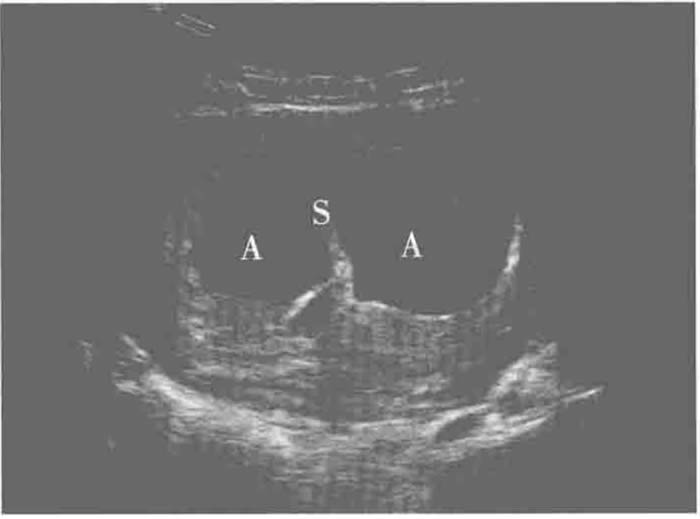

孕11-14周(NT檢查):通過觀察雙胎間羊膜與胎盤交界形(xíng)態進一步確認絨毛膜性。單絨毛膜雙胎呈“T”字(zì)形,雙絨毛(máo)膜(mó)雙胎則顯示“雙峰征”或者“λ征”。

雙胎峰